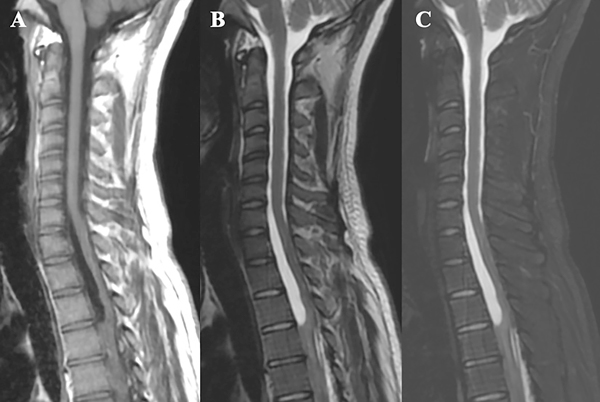

Se presenta el caso de una paciente de 21 años de edad, con antecedentes de infección por VIH, sífilis, consumo de drogas ilícitas y alcohol, que consulta por parestesias en ambos miembros inferiores de 6 meses de evolución, a lo que agrega paraparesia y dificultad en la marcha en los últimos 3 meses, con empeoramiento progresivo. Al examen físico presentaba una paraparesia moderada, hipertonía, hiperreflexia e hipoestesia en todas las modalidades sensitivas en miembros inferiores con nivel sensitivo T4 y signo de Babinski bilateral, así como también dolor dorsal con irradiación a ambos miembros inferiores. En la resonancia magnética (RMN) de columna completa se observaba una imagen a nivel T1 a T3, hipointensa en T1, hiperintensa en T2 y STIR, sin captación de contraste endovenoso, con desplazamiento posterior de la médula espinal y adelgazamiento de la misma (Figura 1 y 2). Se interpretó el cuadro como un quiste aracnoidal asociado a una aracnoiditis adhesiva. En este contexto, debido a la progresión y severidad de los síntomas, se realizó laminotomía T1-T2-T3 y evacuación de la lesión quística en el mismo nivel (Figura 3). Se enviaron muestras de aracnoides a anatomía patológica, la cual demostró “fragmento de tejido dural con fibroesclerosis y vasocongestión”; a su vez se realizaron cultivos de gérmenes comunes, hongos, parásitos, tuberculosis y PCRs virales, los cuales resultaron negativos.

Figura 1: Resonancia magnética de la paciente, se observa lesión quística a nivel T1-T2-T3, con desplazamiento posterior de la médula espinal y adelgazamiento de la misma. A- En secuencia T1 se visualiza la lesión quística hipointensa; B- En secuencia T2, la lesión quística es hiperintensa; C- En STIR la lesión quística también es hiperintensa, correlacionándose con la señal del LCR.